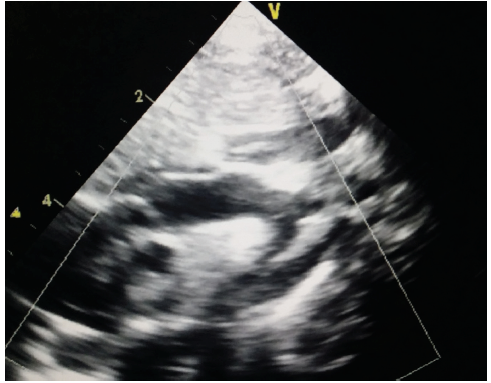

Sheela Madipelli, MD

Coarctation of the aorta (CoA) constitutes approximately 7% of all (CHDs). It is the most commonly missed CHD, and many cases are not diagnosed until adulthood, or death is incorrectly attributed to...